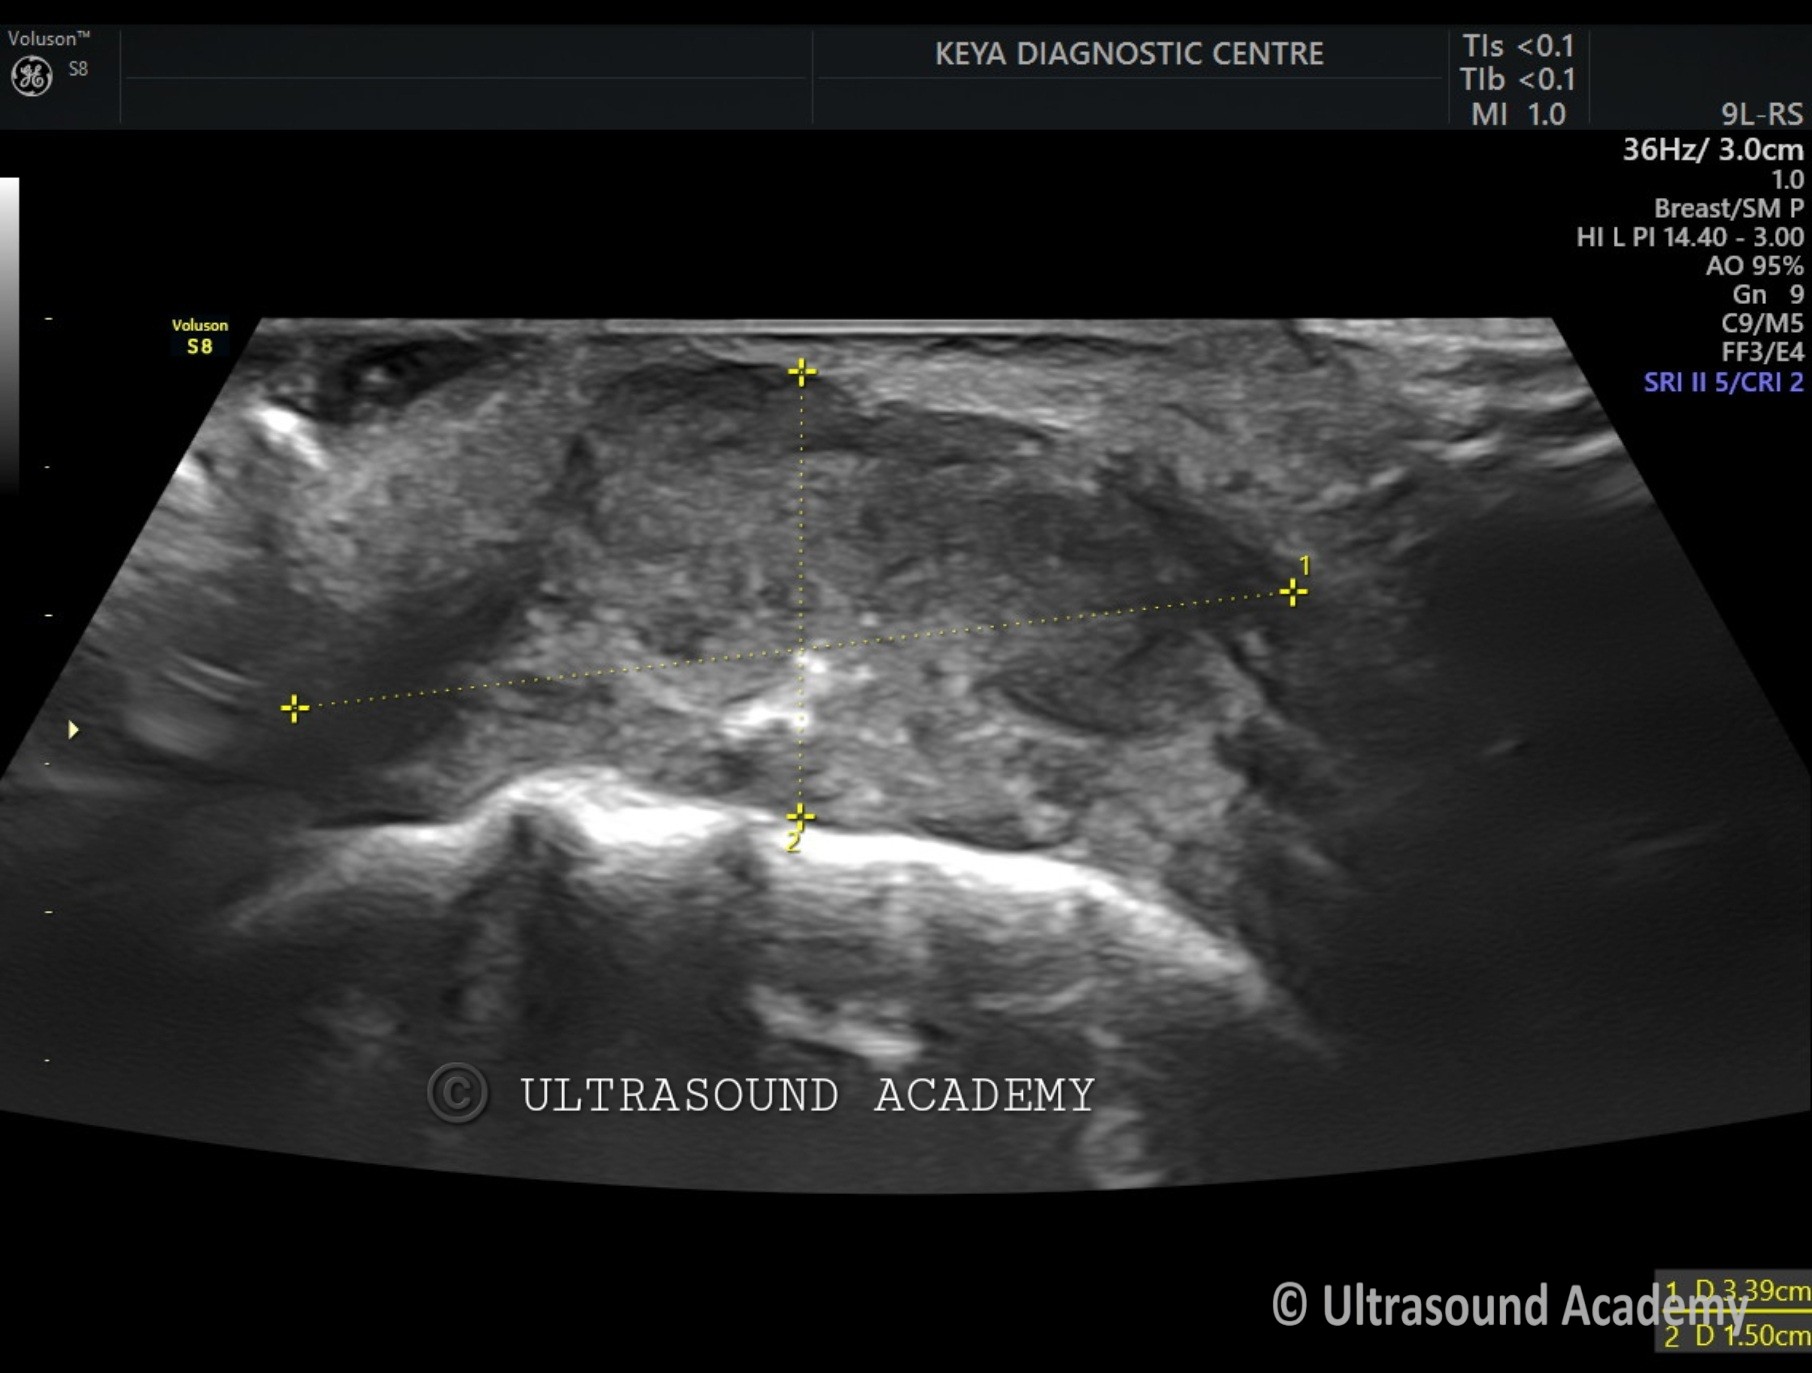

• Hypoechoic irregular mass measuring approximately Approx 1.5 cm in greatest dimension located in the left buccal mucosa.

• The mass shows heterogeneous echotexture with poorly defined borders, invading into the adjacent soft tissues.

• Also an ulcer with air foci seen as hyperechoic specks.